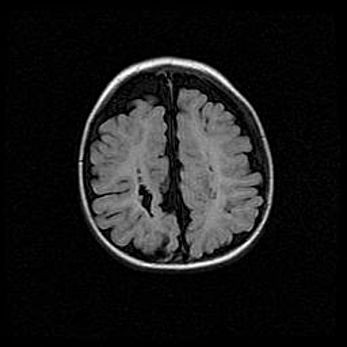

Сообщающаяся гидроцефалия. Кистозная энцефаломаляция головного мозга.

Возраст: 3 месяца 4 дня

Вес: 3100 г

Пол: женский

Окружность головы: 34 см

Срок гестации: 31 неделя

Кистозная энцефаломаляция головного мозга - одна из форм поражения головного мозга в детском возрасте. Характеризуется возникновением множественных и распространённых кист в коре, белом веществе и подкорковых образованиях головного мозга у плодов, новорождённых и детей раннего возраста. Развитие кистозной энцефаломаляции связано с внутриутробной асфиксией и гипотонией, родовой травмой, тромбозом синусов, пороками развития сосудов, инфекциями, сепсисом и другими причинами. Наиболее значимые инфекционные агенты: вирусы простого герпеса, цитомегалии, краснухи, токсоплазмы, энтеробактерии, золотистый стафилококк и другие.